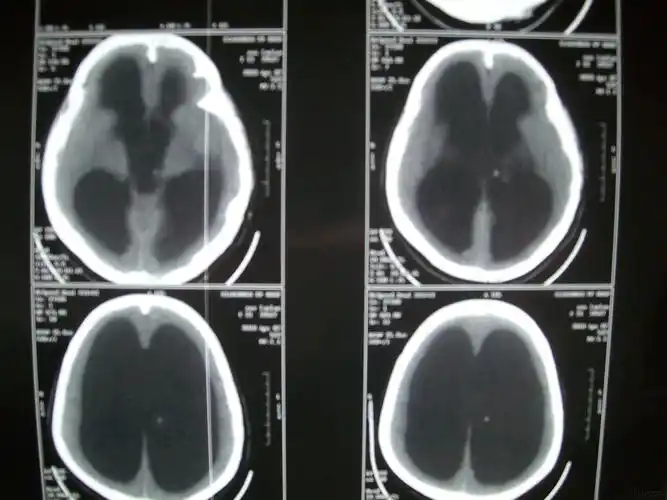

广州医科大学附属第五医院 病例分享:婴幼儿脑积水病例分享

落日征 脑积水